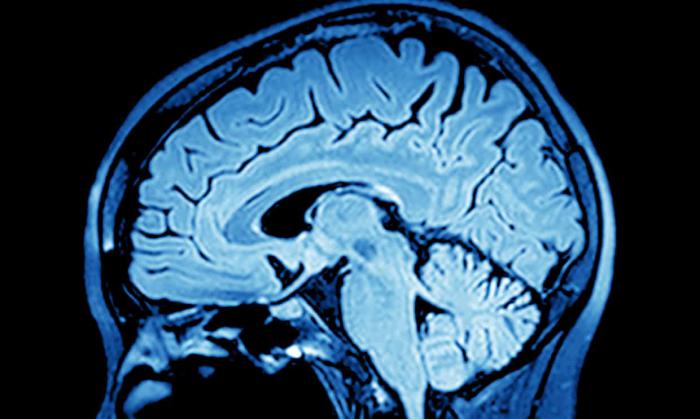

MILLONES DE NIÑOS CON RIESGOS DE DAÑO CEREBRAL DEBIDO A FALTA DE YODO

Casi 19 millones de recién nacidos en el mundo están hoy en riesgo de daño cerebral debido a la deficiencia de yodo, indican informes divulgados por el Fondo de Naciones Unidas para la Infancia (Unicef). Según investigaciones de Unicef y la Alianza Global para una Nutrición Mejorada (GAIN, por sus siglas en inglés), la falta de yodo provoca consecuencias irreparables y resulta la principal causa de daño cerebral prevenible en todo el orbe. Un gran número de enfermedades mentales y factores de deterioro de la capacidad intelectual se asocian a la escasez de ese elemento, por lo cual tales carencias influyen negativamente en el progreso educativo de los países y dañan su desarrollo socioeconómico, señala el informe. (PL)